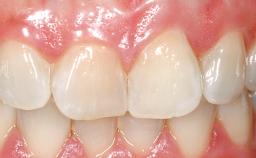

A 30-year-old female patient had lost tooth 21 and was referred to our clinic for consultation and treatment. Due to advanced apical infection, tooth 21 had been extracted two months earlier at another clinic and an acrylic-resin tooth had been bonded to the adjacent teeth. The patient desired implant treatment to avoid any damage to the adjacent natural teeth. While the patient had no history of any systemic disorder, she was a heavy smoker and exhibited medium to advanced periodontitis in the entire jaw. After the initial treatment to achieve a pocket probing depth of less than 4 mm and no bleeding on probing, a decrease in the height of the papillae mesial and distal to the extraction site and overall gingival recession were observed.

Prosthesis Type FDP

Mesio-Distal Space Symmetry +/- 1 mm of contra-lateral tooth

Esthetic Risk High

Soft Tissue Contour and Volume Slightly compromised